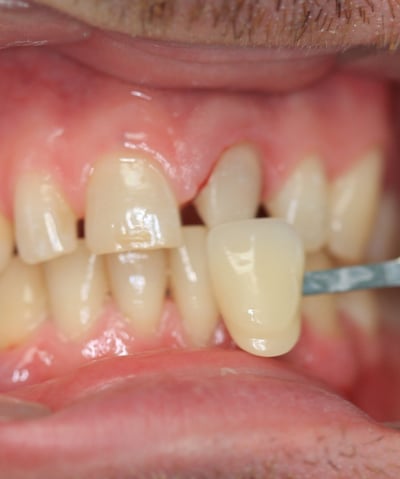

Dopo:

Corona completamente integrata con i denti vicini, senza differenze di colore o forma.

Stabile grazie al nuovo perno moncone in fibra di vetro.

Trattamento endodontico corretto e completato con successo.